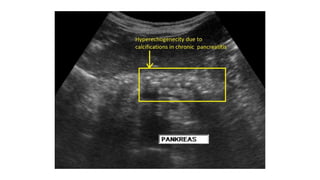

USG Abdomen Detect gallstones

Identify area of necrosis –hypoechoic regions

Transverse ultrasound demonstrates

diffuse enlargement of the pancreas ,

which appears abnormally hypoechoic

• Investigations

-pancreatic calcification on AXR